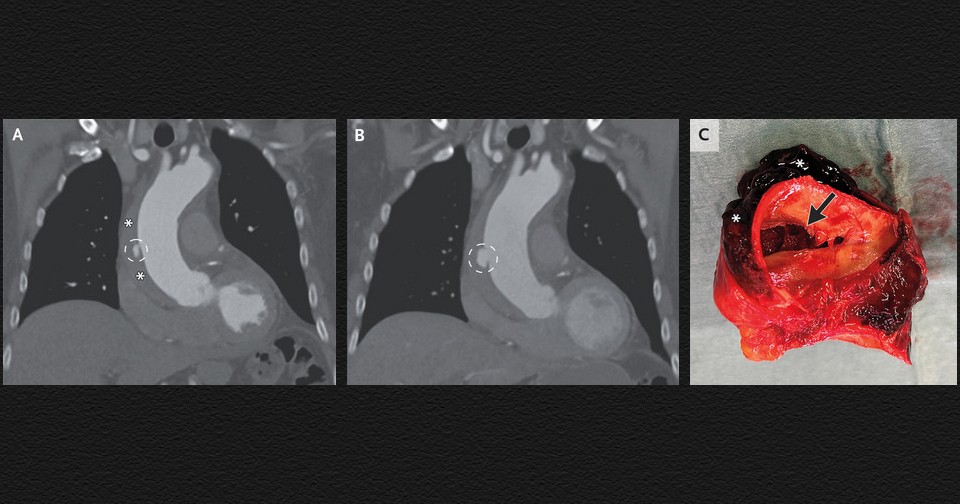

В неотложное отделение нидерландской больницы поступил 80-летний мужчина без особенностей в анамнезе с жалобами на боль в грудной клетке в течение 12 часов и повышением уровня D-димера (маркера недавнего тромбоза). Его артериальное давление было 147/92 миллиметра ртутного столба, пульс — 70 ударов в минуту, а данные осмотра — нормальными. Компьютерная томографическая ангиография легких не выявила тромбоэмболии легочных артерий, однако на ней были видны язвоподобное образование на восходящей аорте и внутристеночная гематома, которая распространялась на дугу и верхнюю часть нисходящей аорты. Врачи Шурд Баувместер (Sjoerd Bouwmeester) и Андре Тьон Юк Тьин (Andrew Tjon Joek Tjien) из Больницы Катарины в Эйндховене поделились этим случаем в The New England Journal of Medicine.

Мужчине поставили диагноз интрамуральной гематомы аорты — формы острого аортального синдрома, при которой кровь поступает в среднюю оболочку сосуда с формированием тромба, выпячивающего сосудистую стенку наружу. Это состояние связано с повышенным риском расслоения аорты. Пациенту начали инфузионную терапию для снижения артериального давления и частоты сердечных сокращений. Боль в груди прошла, и его перевели в кардиологический центр. После беседы с пациентом врачи приняли решение не проводить неотложное хирургическое вмешательство и продолжить наблюдение. На КТ через три для наблюдалось увеличение язвоподобного образования, и мужчине выполнили открытую операцию по протезированию восходящей аорты над коронарными сосудами и половины дуги аорты. В иссеченном участке сосуда помимо гематомы обнаружили разрыв внутренней оболочки и расслоение восходящей аорты. Через шесть дней после операции пациента выписали из больницы.